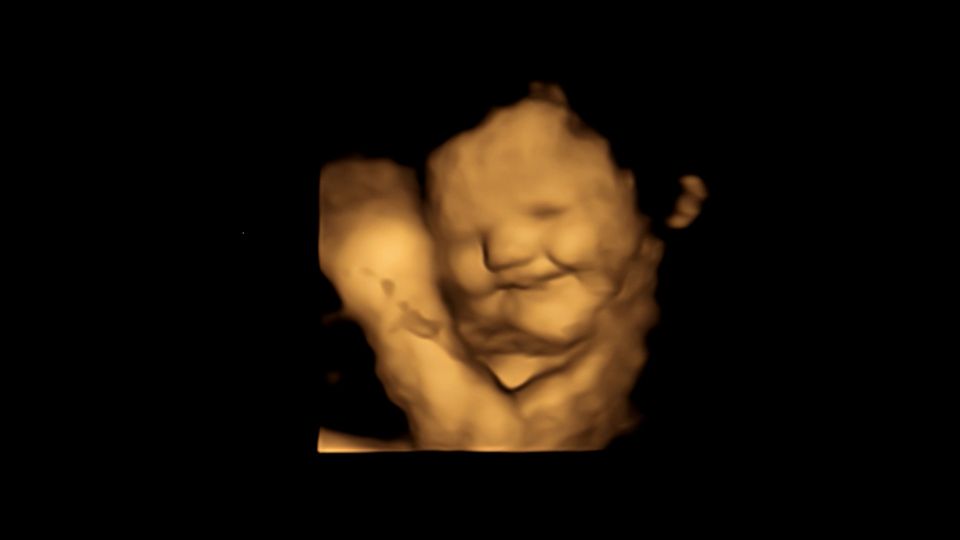

Forschung mit 4D-Ultraschallaufnahmen

Die Forscher zeichneten mithilfe von 4D-Ultraschallaufnahmen bei 100 Frauen die Gesichtsausdrücke ihrer Babys in der 32. sowie 36. Schwangerschaftswoche auf. Die Mütter erhielten rund 20 Minuten vor dem Scan eine Kapsel mit rund 400 Milligramm Karotten oder 400 Milligramm Kohlpulver und nahmen zudem eine Stunde zuvor nichts zu sich, das Geschmack enthält. Gesichtsreaktionen der Föten wurden mit denen einer Kontrollgruppe verglichen, die weder Karotten noch Kohl erhalten hatten. Ergebnis: Selbst kleine Mengen mit Karotten- oder Kohlgeschmack reichten aus, um eine Reaktion auszulösen.